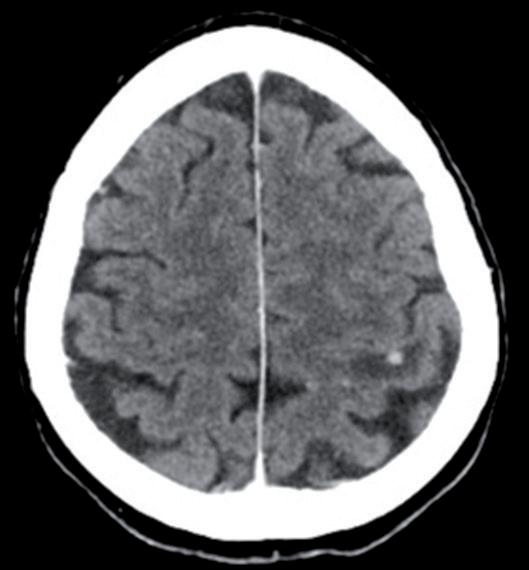

Alla RMN encefalo del 18/02/2022, in sede cerebellare sinistra si conferma la presenza di alterazione sospetta in senso ripetitivo di 15 mm, adesa alla dura madre.

Si evidenzia alterazione osteostrutturale patologica della teca cranica in sede temporo-parietale destra associata a ispessimento lineare della meninge adiacente (figura 3).

TC e RMN encefalo con mdc, febbraio 2022.

Figura